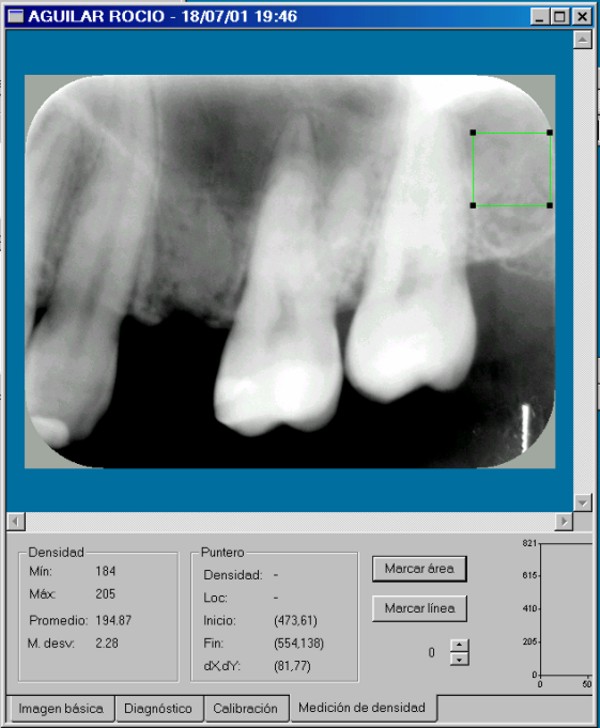

Hubiera sido necesaria la comparación osteodensitométrica entre la zona a implantar y otras zonas maxilares.(DIAPO 8-9-10)

DENSIDAD PROMEDIO:194.87 DENSIDAD PROMEDIO:158.49

DIAPO 8 DIAPO 9

DENSIDAD PROMEDIO:168.5

REF 1